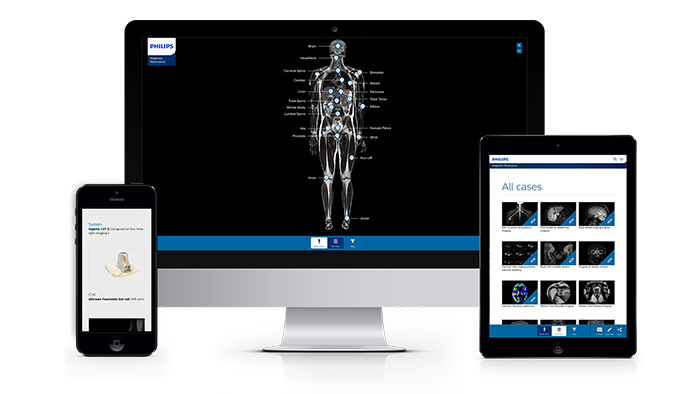

Von anderen Anwendern lernen

Wenden Sie die Best Practices anderer Anwender an, um das Maximum aus Ihrem System herauszuholen.